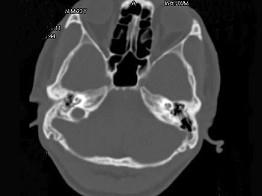

男,23岁,右耳流脓十余年,右外耳道流脓,鼓膜穿孔,CT检查如图,最可能诊断为 ( )

• A.中耳癌

• B.嗜酸性肉芽肿

• C.(海绵化期)耳硬化症

• D.中耳乳突结核

• E.慢性中耳乳突炎

答案: E